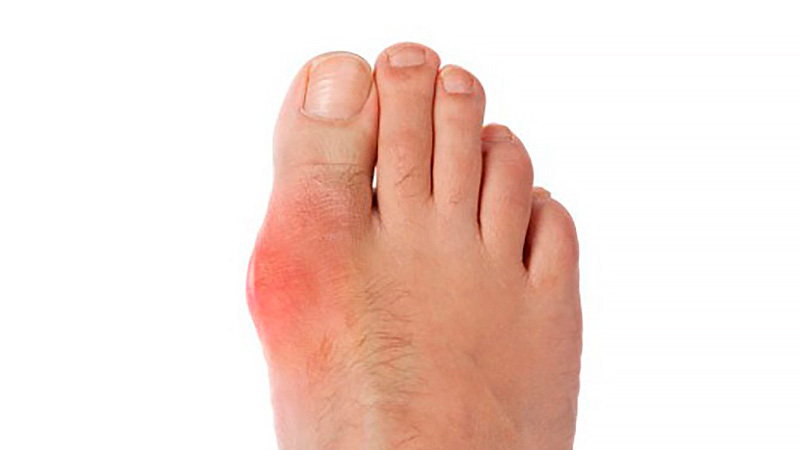

En estos datos basados ​​en la población, ni el inicio de alopurinol, ni el logro del nivel de objetivo de uricemia, ni el aumento de la dosis de alopurinol se asociaron con una mayor mortalidad en pacientes con gota y ERC concurrente. Annals of Internal Medicine, 25 de enero de 2022.

Asociación de enfermedad renal crónica con el uso de alopurinol en el tratamiento de la gota

JAMA Intern Med, 8 de octubre de 2018. En este estudio de cohorte de base poblacional del Reino Unido , el uso de alopurinol en pacientes con gota no aumentó el riesgo de disminución de la función renal, y se asoció significativamente con un riesgo 13% menor a dosis de 300 mg o más por día. Lo que significa que el alopurinol no parece estar asociado con una disminución de la función renal, y los médicos deben considerar otros contribuyentes potenciales cuando se enfrentan a una disminución de la función renal en pacientes con gota.